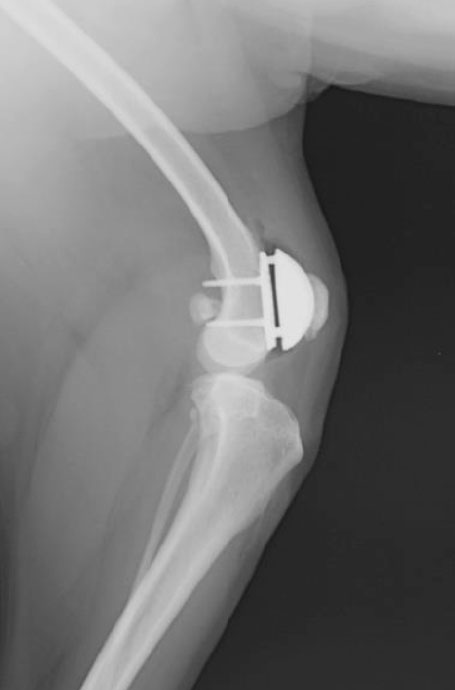

膝蓋骨滑車溝置換術

滑車溝をインプラントに置き換えて、膝関節を安定化。

PGR( Patellar Groove Replacement)とは、犬の膝蓋骨内方脱臼や外方脱臼に対して滑車溝を人工のインプラントに置き換える手術方法です。滑車溝軟骨損傷が激しい症例などが適応になります。

PGRインプラントは大腿骨に設置したベースプレートと、摩擦・摩耗を最小限に抑えられるよう滑らかにコーティングされた人工溝を組み合わせた構造になっています。ベースプレートは大腿骨の海綿骨にチタン製のネジで固定することで骨吸収を促進させ、安定化を実現しています。

術後